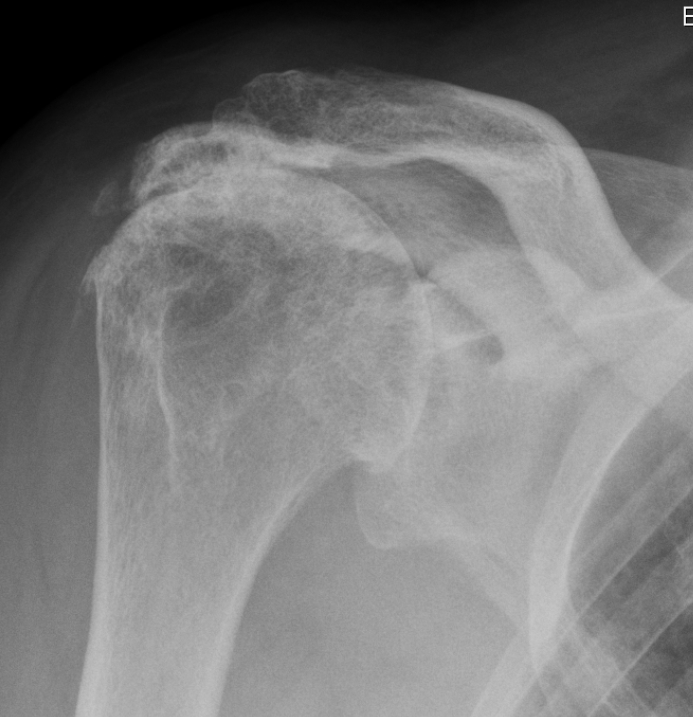

Beschreiben Sie die Befunde auf dem vorliegenden Röntgenbild der Schulter und geben Sie die wahrscheinlichste Ursache für die Befunde an.